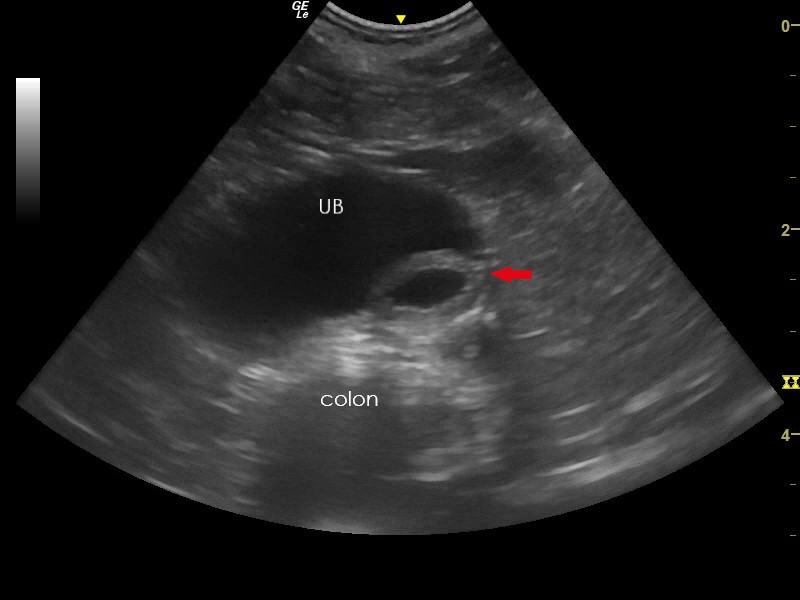

In rare cases, congenital abnormalities can be observed ultrasonographically. Ureteroceles are congenital cystic dilations of the of the terminal ureter. On ultrasound they appear as round, thin walled structures projecting into the bladder lumen and filled with anechoic fluid (Figure 8). Ultrasonography can also detect changes associated with ectopic ureters. These include dilated ureters travelling beyond the dorsal bladder neck (Figure 9) and the absence of ureteric jets from the ureteric papillae at the trigone area. However, diagnosis of ectopic ureters can be challenging and alternative diagnostic tests such as contrast enhanced computed tomography or cystoscopy can be utilised8.

Figure 8. Ureterocele – A thin-walled cystic structure (ureterocele, red arrow) is present in the wall of the trigone region of the urinary bladder (UB). The affected ureter can insert at a normal position (orthotopic) or may be ectopic.